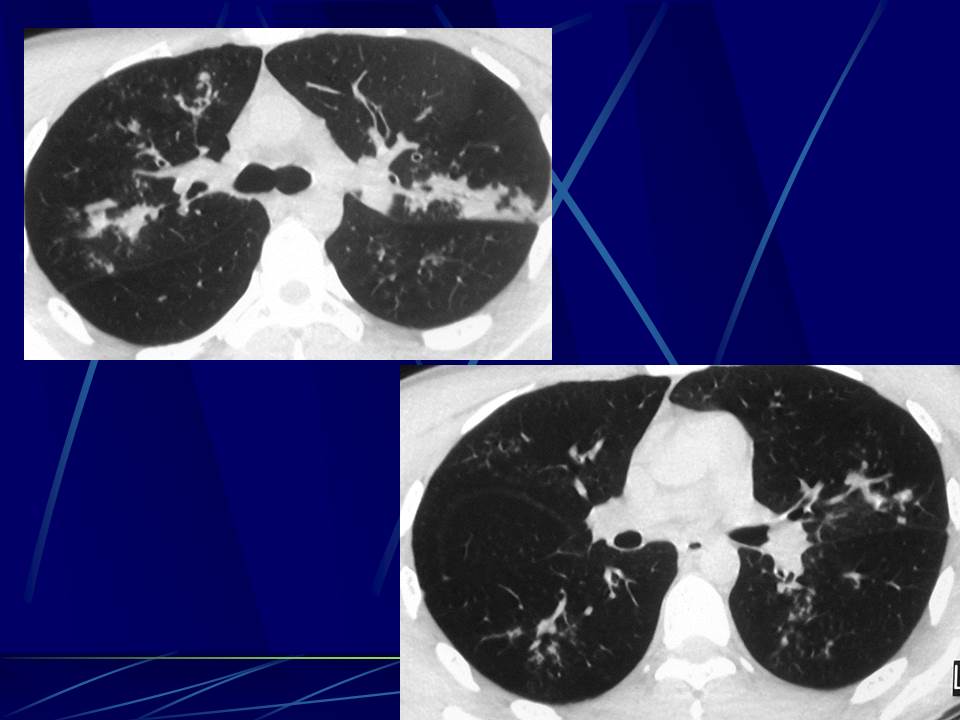

肺部真菌感染影像学分析